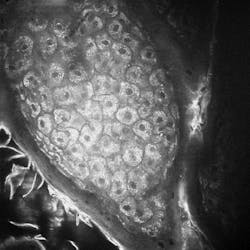

But my favorite demo at the show was found in the exhibit of the German Biophotonics Research Program. I watched as JenLab’s multiphoton tomography system—which incorporates a femtosecond laser—produced incredible, cellular-resolution images of the skin of a volunteer subject.The answer is here